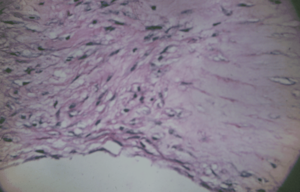

عينة من القرنية المخروطية أخرجت بعد ست سنوات من التشخيص: سدى رقيقة، والتجاعيد على السطح الخلفي

على الرغم من القدر الكبير من البحث عن مسببات القرنية المخروطية إلا أن السبب لا يزال غير واضح.[14] عدة مصادر تشير إلى أن القرنية المخروطية المرجح تنشأ من عدد من العوامل المختلفة: الوراثية والبيئية أو الخلوية، أي من التالية قد تؤدي إلى التسبب بظهور المرض .[19][20][21] تكون بداية المرض من تحلل طبقة بومان، [6] التي تقع بين ظهارة القرنية والسدى. وعند تلامس الطبقتين يؤدي ذلك إلى التغيرات الخلوية والهيكلية في القرنية التي تؤثر سلبا على سلامة المريض و تسبب انتفاخا وتندبا . في أي حالة مفردة من القرنية المخروطية يمكن ملاحظة مناطق من الترقق ومناطق متحللة تتواجد مع المناطق التي يحدث فيها التئام للجروح و يعد التندب جانبا من جوانب تدهور القرنية . ومع ذلك، تشير دراسة أخيرة من مراكز عدة بأن التآكل بواسطة العدسات اللاصقة قد تزيد من احتمال حدوث هذه النتيجة بمعامل أكثر من الضعف .[22][23]